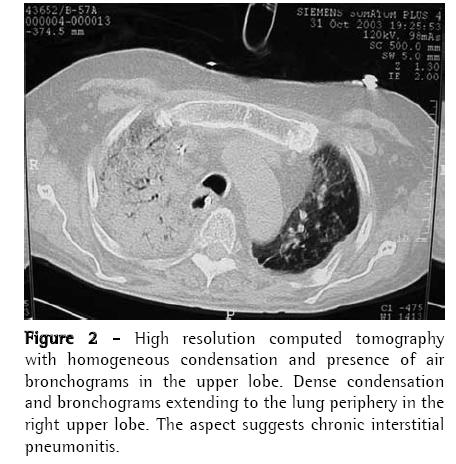

A 56-year-old man diagnosed with IPF (using clinical, functional, tomographic and pathological criteria) five years prior, progressively evolved to dyspnea upon exertion and intense difficult-tocontrol cough with sparse mucoid expectoration. In the month preceding the lung transplantation, he presented hypoxemia and hypercapnia (arterial blood gas analysis with a PaO2 of 57 mmHg and arterial carbon dioxide tension of 45 mmHg at rest on room air at sea level), diffusing capacity of the lung for carbon monoxide at 29% of the predicted value, forced vital capacity of 40.8% (1.41 L), and forced expiratory volume in one second of 52.6% (1.31 L). Pulmonary perfusion scintigraphy revealed arterial flow of 76.7% for the right lung and 23.3% for the left lung. The laboratory tests for collagen-related diseases and the epidemiological investigation of known interstitial diseases were negative. During the five years of outpatient monitoring, the patient had been treated with corticosteroids (prednisone, 0.25 to 1 mg/kg/day), immunosuppressive agents (azathioprine or cyclophosphamide, 0.5 to 2 mg/kg/day), and an antifibrotic/immunomodulatory agent (interferon-γ1b) for four months. The transplantation was unilateral at left, corresponding to the minimal arterial perfusion and the greater intensity of the interstitial involvement according to the high-resolution computed tomography (HRCT) scan. Immediately after surgery, the patient evolved to thoracic instability due to the fracture of three ribs as a result of the osteopenic rib traction during the closure of the incision. He also presented ischemia of severe pulmonary reperfusion (arterial blood gas analysis with a PaO2/fraction of inspired oxygen ratio = 124). The patient was tracheostomized and remained on invasive mechanic ventilation (MV) for ten days, progressively recovering from hypoxemia. The immunosuppressive regimen began with 5 mg/kg of cyclosporine (12/12 h), 0.5 mg/kg/day of prednisone, and 2 mg/kg/day of azathioprine. In addition, anti-basiliximab interleukin-2 antibody was administered on postoperative days 1 and 4. Anti-methylprednisolone antibody (1 g) was also administered postoperatively. The patient was discharged from the intensive care unit to the semi-intensive care unit. However, on the eighth day in the semi-intensive care unit, he presented exacerbation of dyspnea, accompanied by the return of the dry cough and progressive crackling rales throughout the right hemithorax, and was therefore re-admitted to the intensive care unit. The patient was again submitted to an HRCT scan. In addition, fiberoptic bronchoscopy with bronchoalveolar lavage (BAL) was performed, together with transbronchial biopsy of the left lower lobe and the right upper lobe. All cultures tested negative, the BAL fluid presented a neutrophilic pattern, without eosinophils or hemosiderin-laden macrophages, and the histopathological analysis was inconclusive. A pulmonary arteriogram was performed, followed by thoracoscopic lung biopsy in three different regions of the right upper lobe to ensure that the disease was representative (Figures 1 and 2). The pulmonary arteriogram did not demonstrate thromboembolic disease. The biopsy culture was negative for bacteria, fungi, and mycobacteria. Herpes simplex virus and cytomegalovirus tests were also negative. Direct immunofluorescence for Chlamydia pneumoniae, Legionella pneumophila, and Mycoplasma pneumoniae, as well as for antigenuria for L. pneumophila serotype 1, were negative. The histological study of the biopsy of the three right lung areas showed an exclusive pattern of UIP, similar to the left native lung (Figure 3). Pulse therapy with 1 g of methylprednisolone was performed for three consecutive days. The patient remained on invasive MV, then evolved to sepsis caused by infection with Klebsiella pneumophila and Pseudomonas aeruginosa. On day 141 of the hospital stay, after the patient had been on invasive MV and using noradrenaline (0.2 µg/kg/day) for 109 days, transplant of the right native lung was carried out - bilateral sequential transplantation with more than a month interval - regardless of the relative contraindications: high dose of corticosteroid (>20 mg/day), MV, and sepsis treatment. (6)

The radiological imaging demonstrated condensation in the middle, upper, and lower right lobes, and the established diagnosis was IPF exacerbation in the native lung, mainly characterized by the UIP histological aspect (nonuniform and multifocal infiltrate, with inflammatory and fibrous thickening of the alveolar interstitium, pulmonary cysts, peribronchiolar fibrosis, alveolar hyperplasia, and absence of hyaline membranes), and the absence of microbial increase in lung tissues and cardiovascular decompensation. It is known that, in IPF, the lung becomes progressively collapsed, which can simulate images of pulmonary condensation. The accelerated variant of IPF has recently been described and should have its diagnosis characterized by ruling out other causes of exacerbation. The literature mentions, in unilateral lung transplantation, chronic progression of IPF in the native lung. However, there have been no reports of acute progression. This is the first case described in the national literature as IPF in its accelerated phase.